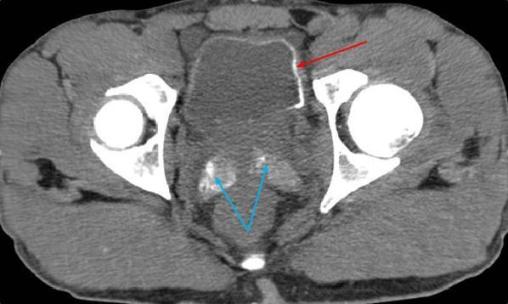

Devant ces éléments évocateurs de bilharziose urogénitale, un examen parasitologique des urines (EPU) est demandé, confirmant la présence d’œufs de Schistosoma haematobium. Un traitement par praziquantel est débuté et une cystoscopie est organisée secondairement par l’urologue. La cystoscopie met en évidence deux lésions infracentimétriques du dôme et du col vésical d’aspect cicatriciel (fig. 2). La cytologie urinaire élimine un carcinome urothélial de haut grade mais ne peut exclure une tumeur papillaire de bas grade.